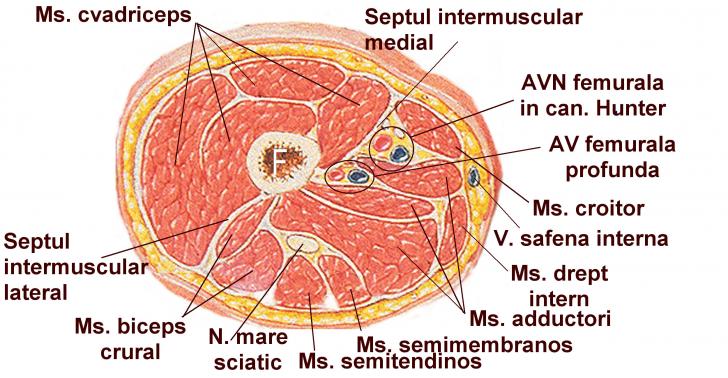

AMPUTATIA DE COAPSA

AMPUTATIA DE COAPSA I. DEFINITIE Amputatia coapsei este interventia chirurgicala prin care se realizeaza indepartarea membrului inferior de la nivelul treimii inferioare sau mijlocii a coapsei. II. ISTORIC ChiruCiteste tot ... 6841 cuvinte

Dimensiune mare

+ cu imagini |